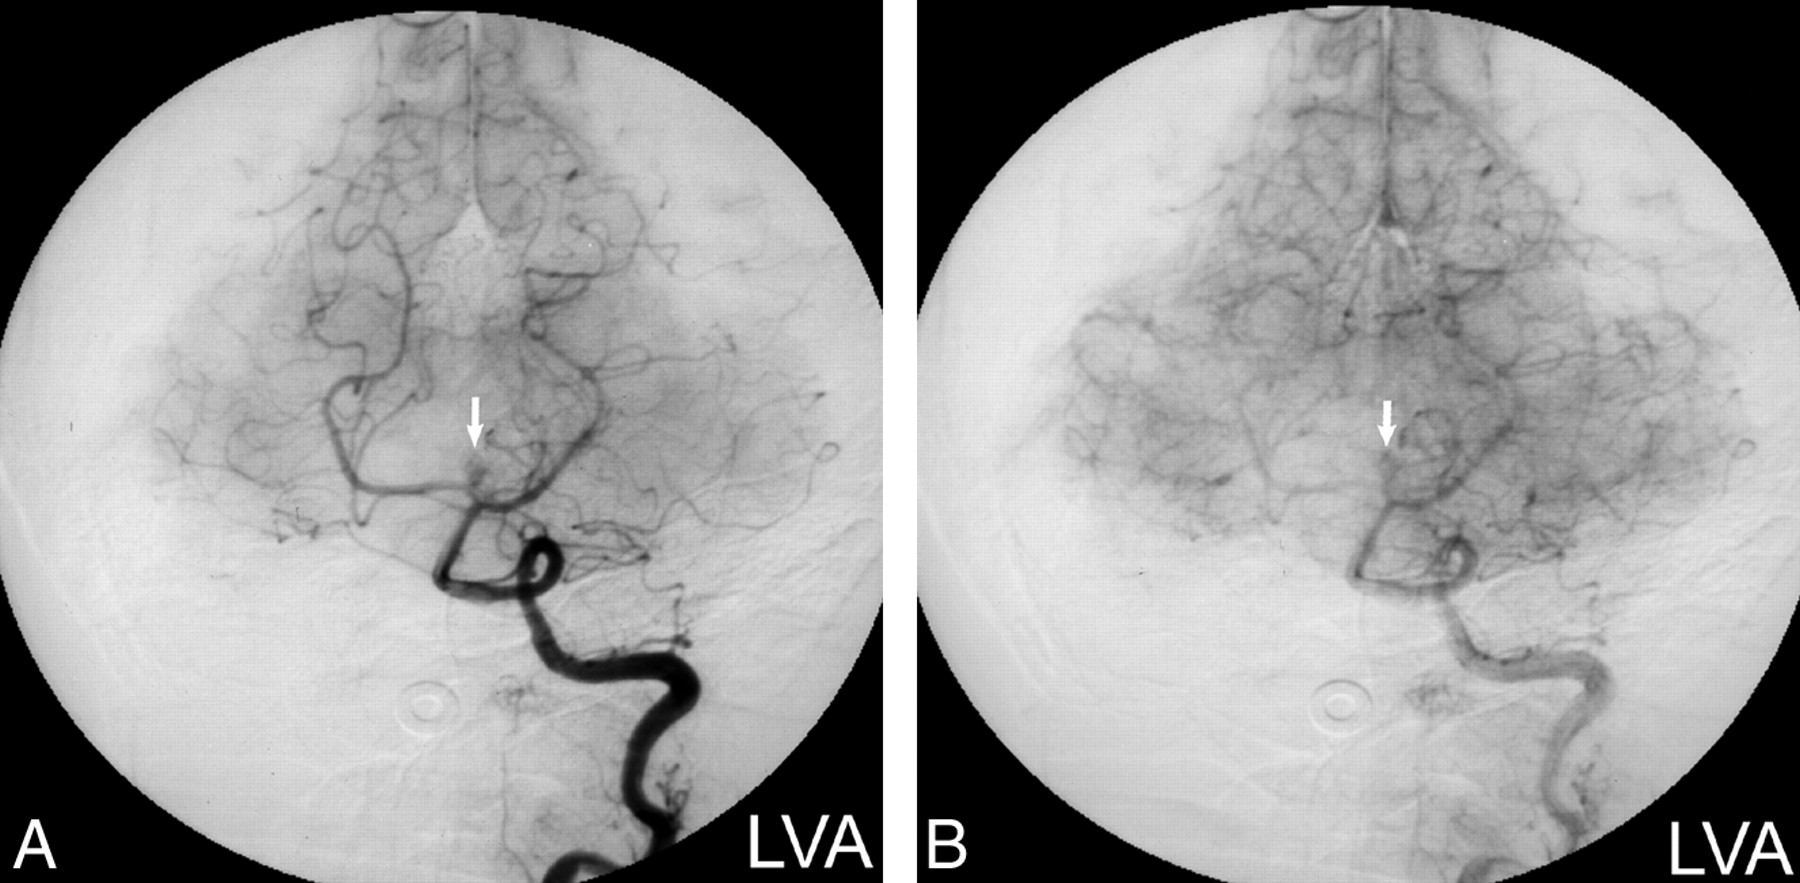

Digital subtraction angiograms.

A, Left vertebral artery injection (arterial phase) shows vascular enhancement of the mass (arrow) in a pattern atypical for aneurysm.

B, Left vertebral artery injection (capillary phase) confirms a persistent blush (arrow) that would be unusual for an aneurysm.

MR imaging revealed a 1-cm heterogeneous extraaxial mass within the interpeduncular cistern that deformed the left cerebral peduncle. On nonenhanced T1-weighted images (Fig 1A), the mass had mixed intermediate (relative to gray matter) and high signal intensity areas. The mass displayed mixed intermediate and low signal intensity on conventional spin-echo T2-weighted images (Fig 1B). Intravenous administration of gadopentetate dimeglumine produced scattered areas of mild enhancement (Fig 1C). A presumptive clinical diagnosis of a partially thrombosed basilar artery aneurysm was made on the basis of the MR imaging characteristics, location, and clinical symptoms. Subsequent digital subtraction angiography, however, did not confirm the presumptive diagnosis of aneurysm, with the mass displaying a delayed blush more typical of a vascularized soft tissue mass (Fig 2A and B). CT imaging obtained to clarify the disparity between MR imaging and angiography demonstrated areas of marked hypoattenuation (-8 HU) on the nonenhanced series (Fig 3A) characteristic of fat and heterogeneous enhancement (28–70 HU) (Fig 3B), which corresponded to the blush noted at digital subtraction angiography.